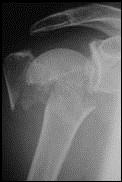

Shoulder fracture before surgery